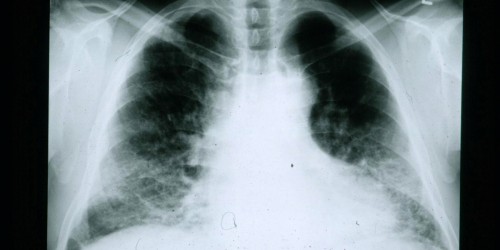

Good Morning America showed a medical case in which Viagra was sucessfully used to treat the collapsed lung of an infant. About a year ago, a study came out showing that viagra helped women with pulmonary hypertension. Is there any indication that Viagra could help someone with Stage III or IV pulmonary sarcoidosis?